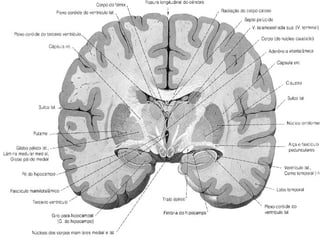

Anatomia cerebral

Gânglios da Base

• Tecido de substância cinzenta sub cortical

simétrico, localizados nas superfícies inferiores

dos hemisférios cerebrais.

• Núcleos lenticulares ( putamen e globus pálido),

núcleo caudado, claustro e amígdala.

Núcleos lenticulares.

• Biconvexo , envolto por substância branca,

• Cápsula externa ( separa do Claustro ),

• Cápsula Extrema ( separa claustro da ínsula ),

• Cápsula interna ( braço anterior , joelho e

braço posterior ).

• Putamen ( lateral , maior e mais escuro ) / globo pálido.